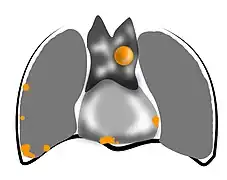

Le thymus est un organe intrathoracique, situé dans la loge thymique, dans le médiastin antérieur[3]. Cette zone est située entre les poumons, et à l'avant du cœur et des gros vaisseaux tels que l'aorte et ses branches[4]. Le thymus est constitué de deux lobes unis par le milieu, sauf à leurs extrémités supérieure et inférieure, appelées les cornes thymiques[5]. Le thymus comprend une région superficielle, appelée « cortex », et une région profonde, appelée « médulla ». Il grandit de la naissance jusqu’à la puberté, puis régresse progressivement[6].

Les thymomes sont rares, avec une fréquence de 0,15 cas pour 100 000 habitants et par an dans le monde[14],[15]. On recense environ 250 nouveaux cas par an en France[16],[17]. Il s'agit toutefois des tumeurs du médiastin antérieur les plus fréquentes (50 % des cas sont des thymomes). Plus de 90 % des tumeurs thymiques sont situées dans le médiastin antérieur (la région située entre les poumons et à l'avant du cœur et des gros vaisseaux), les autres étant dans la région cervicale ou les autres régions du médiastin[14].